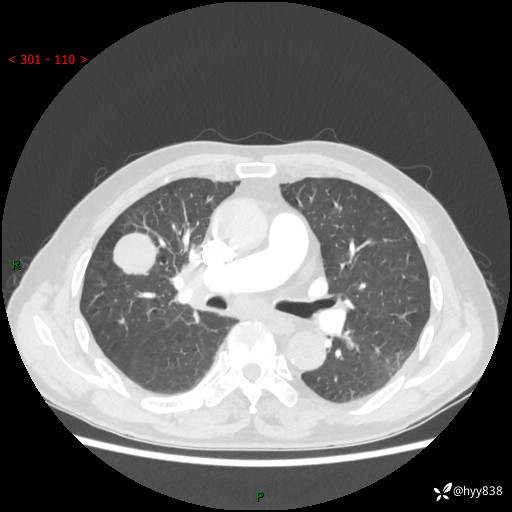

69岁/男,间断咳嗽伴气促、下肢水肿。临床拟诊肺栓,偶发肺均质强化结节--结果公布

【患者信息】:69岁/男

【主诉】:间断咳嗽伴气促、下肢水肿2周

【现病史及既往史】:患者2周来无明显诱因出现咳嗽,咳少量白痰,不易咳出,伴有气促,呈间断发作,症状与活动费力相关,以夜间为甚,不能平躺入睡,偶有憋醒,无胸闷胸痛、无发热、无头晕、头痛等不适,伴有双下肢中度水肿,就诊于当地县人民医院门诊,完善相关检查提示:左下肢深静脉血栓形成,未予以特殊处理,今患者为求进一步诊治来我院就诊,拟“心衰”收入我科。 起病以来,患者精神、饮食、睡眠可,大小便如常,体力明显下降,体重未见明显减轻。

【检查】:胸部CT增强